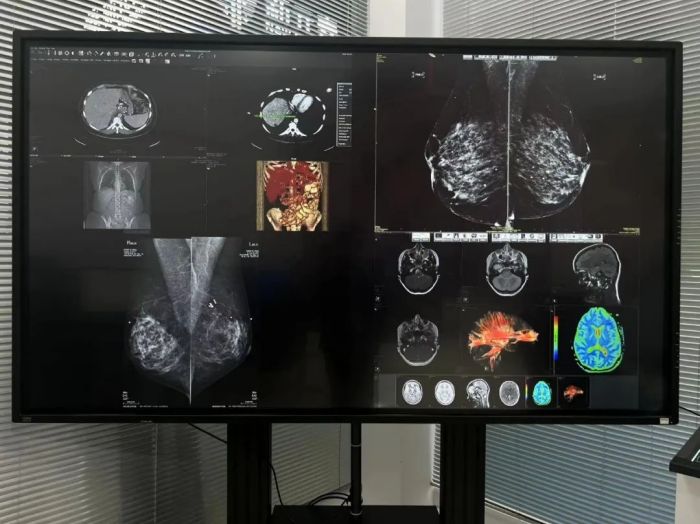

随着医疗信息化的迅速发展,医学影像已成为医疗数据的重要组成部分。研究报告显示,医院需处理信息数据量每年增长30%,其中90%是医学影像数据。巴可现场展示了面向未来的一体化阅片影像中心解决方案,满足当代医疗需求。一体化、智能化、多级协作等面向未来的功能,提高医疗诊断效率和准确性。

巴可一体化阅片影像中心可满足多种场景操作需求,包括最高水平诊断和工作效率、科室内外的互联互通等。

Coronis Uniti 12MP

Coronis Uniti 12MP 诊断显示系统是全球首台12MP多模态显示器,超过行业标准的高分辨率,卓越的2D和3D能力,可显示静态成像和动态成像,可应用于乳腺成像和 PACS 。

多模态显示器 Coronis Fusion

多模态显示器 Coronis Fusion采用全新、轻巧节能设计,具有高亮度、高对比度图像质量,可快速查看更多病灶细节,同时还可减少视疲劳,有效提高诊断准确性和阅片效率。